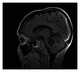

T1-hypointense intracranial lesion

T2*-weighted imaging is an MRI sequence to quantify observable or effective T2 (T2* or "T2-star"). In this sequence, hemorrhages and hemosiderin deposits become hypointense. [Source: Wikipedia ]